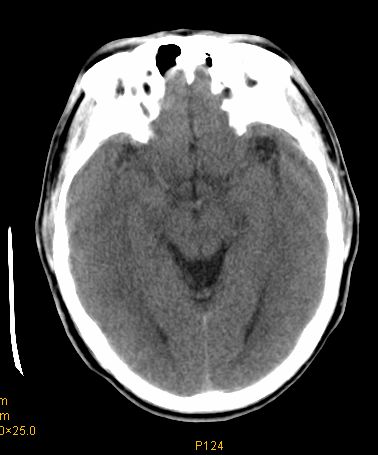

男 42岁 头痛20天

左顶叶见片状低密度影,边界不清,内见斑片状等密度影。考虑转移性肿瘤可能性大,建议ct增强或mr增强扫描。建议胸部检查,排除肺部病变。

左顶叶见片状低密度影,内似见结节状略高密度影,建议增强扫描。

左侧顶叶低密度灶,性质待定;建议行ct增强扫描或mri检查。

左顶叶见片状低密度影,边界不清,内见斑片状等密度影。考虑转移性肿瘤可能性大,建议ct增强或mr增强扫描。建议胸部检查,排除肺部周围型腺癌。

左侧顶叶低密度灶,性质?建议行ct增强扫描或mri检查。

左侧顶叶低密度灶,胶质瘤或转移瘤,建议ct增强扫描或mri检查。